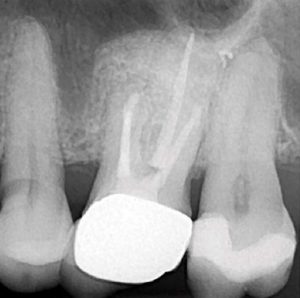

Eighteen months later, the patient returned for a second reassessment appointment (Figure 4 ). Tooth LR2 was slightly sensitive to percussion and the overlying gingival tissues were inflamed.

Sutures were removed in seven days and the patient reappointed for reassessment. The re-evaluation radiograph taken at nine months showed substantial osseous regeneration (Figure 16) and a post-operative CBCT scan was taken after one year, showing complete bone regeneration and continuity of the buccal plate. (Figure 17).